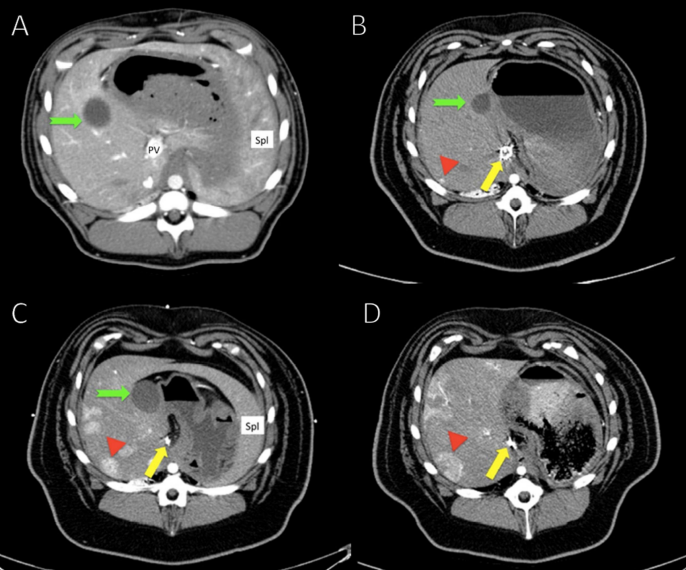

肝癌模型